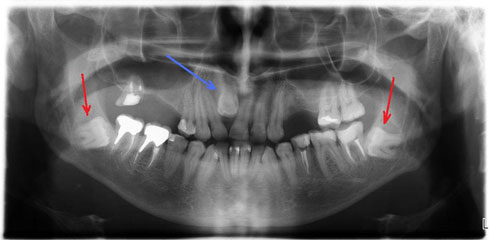

В одной из прошлых заметок я показывал одну из основных причин развития хронического воспаления в костной ткани вокруг корня зуба, а именно пропущенные во время первичного лечения каналы. Сегодня я покажу еще 2 случая, примерно похожих, когда пришлось столкнуться не только с ошибками при первичном лечении каналов, но и вдобавок к этому с неправильно выбранной методикой реставрации "мертвых" зубов.

Первую часть задачи по спасению удалось выполнить. Теперь этот зуб будет находиться под наблюдением в течение 3-4 месяцев. После этого срока будет сделан контрольный рентген, который должен показать, насколько успешной была наша попытка спасти зуб от удаления, а именно, мы ожидаем уменьшения очага воспаления вокруг корня. Если эта тенденция будет явно заметна, только тогда будет принято окончательное решение о восстановлении зуба коронкой. А на очереди у этой пациентки сосед-«близнец» этой многострадальной 6-ки, 7-ой нижний зуб. Что тут скажешь?.. Узнаваемый почерк предыдущего доктора.

Что касается корневых каналов, то именно здесь и были основные сложности. Оба канала были не слишком здорово обработаны и запломбированы, в результате чего на обоих корнях появились гранулемы.